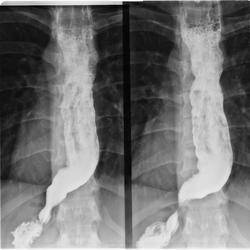

- рентгенологическое контрастное исследование – пациенту предлагают проглотить порцию контрастного вещества (сульфата бария), после этого делают серию рентгенологических снимков. По ним выявляют скорость перемещения сульфата бария по пищеводу и освобождения от него конечного участка пищевода;

- Рентгенография грудной клетки. Обследование начинается именно с данного исследования. В случае выявления на рентгенограмме тени расширенного пищевода с жидкостным уровнем назначается рентгенография пищевода, предполагающая предварительный прием бариевой взвеси. Если имеет место ахалазия кардии, то становится заметным сужение конечного отдела пищевода, а также расширение участка, располагающегося выше.

У больных с кардиоспазмом при рентгенологическом исследовании выявляют усиление моторики пищевода с выраженными сегментарными сокращениями, при ахалазии кардии — снижение моторной активности пищевода (отсутствие первичной перистальтики в дистальных 2/3 пищевода).

Рентгенологическими признаками кардиоспазма являются расширение пищевода в той или иной степени с наличием «узкого сегмента» в терминальном его отделе. Стенки пищевода, в том числе и в суженной части, сохраняют эластичность. В расширенном пищеводе натощак определяется значительное количество жидкости.